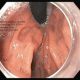

MR AS,male /55 yr was operated for distal gastrectomy for carcinoma stomach 7yrs back.He had recurrence 12 months back when he got total gastrectomy with roux-en-y esophageal-jejunal anastomosis.The jejunum was made into a J-shaped using staplers and anastomosed.He underwent chemotherapy.Recently,patient had absolute dysphagia to solids and liquids he could take inadequately.His PET scan confirmed recurrence at the site of anastomosis.

His gastroscopy was done and the scope could not be negotiated across tha anstomosis.The wire could not be passed under fluoroscopy for dilatation with another gastroenterologist .

I could pass a wire and dilate the esophago-jejunal anastomosis with placement of a covered metallic self expandeble stent for palliation of dysphagia with half of the covered stent in the j-shaped jejunum and half proximally.